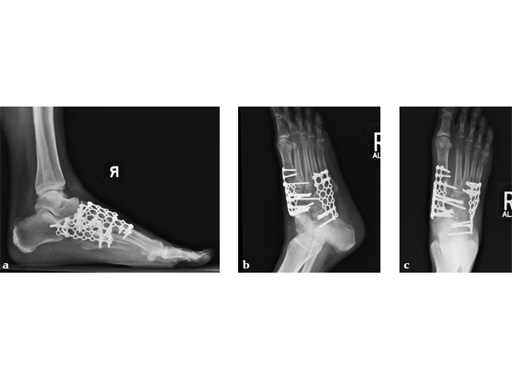

As isolated fusion of the talonavicular joint is often hard to achieve, a 4.0 mm lag screw a plus X-plate was used (see Fig. 2a-c).

The patient was treated with arthrodesis of the talonavicular and subtalar joints. The compression/ distraction device was used to restore the length of the medial column. The articular surface of the subtalar joint was prepared arthroscopically. The talonavicular joint was debrided then packed with a tricalcium matrix. Length was maintained using a locking X-plate. The subtalar joint was then fixed with a 6.5 mm headless compression screw.